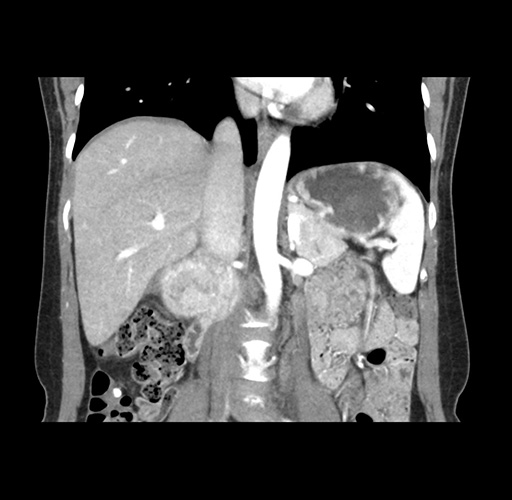

Imaging Analysis

Look through the patient's CT scan to identify any areas of concern for the necessary procedure.

Based on your CT findings, which issue(s) would give reason for "planned slowing down moment(s)" in this case?